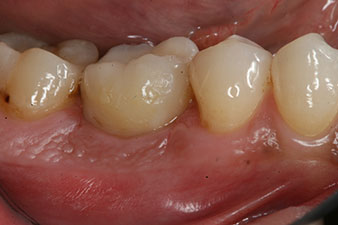

Die Abschlussbilder zeigen die verschraubte monolithische Kompositkrone in situ und die Röntgenkontrolle (Abb. 9 und 10) (6).

Kompositkrone

Abb. 9: Die definitive Kompositkrone wurde im Labor auf ein PEEK-Hybrid-Abutment geklebt und kann sofort verschraubt werden.

Röntgenkontrolle

Abb. 10: Die Röntgenkontrolle zeigt die erfolgreiche Osseointegration und die spaltfrei verschraubte Krone.